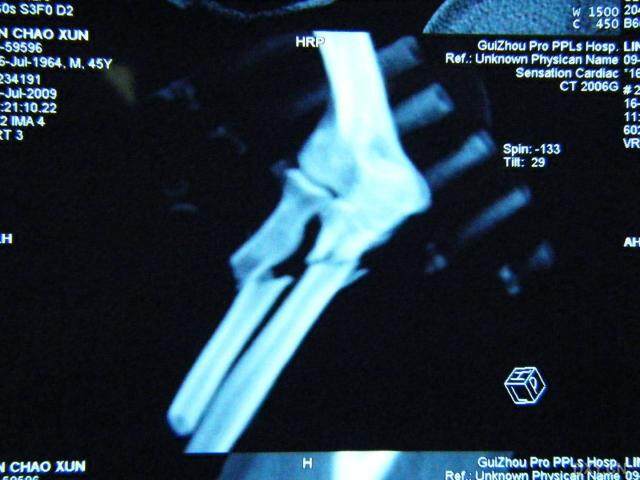

經(jīng)過醫(yī)生的診斷,小明被確診為尺橈骨融合,這是一種骨骼疾病,會導(dǎo)致尺骨和橈骨無法正常活動,聽到這個消息后,小明和他的朋友們都感到有些緊張和害怕,但他們并沒有放棄,而是選擇相互鼓勵,共同面對這個挑戰(zhàn)。

在醫(yī)生的介紹下,他們了解到了一種最新的尺橈骨融合治療方法——通過微創(chuàng)手術(shù)進行骨骼融合的新技術(shù),這種方法不僅減少了手術(shù)風(fēng)險,還能更快地恢復(fù)活動能力,雖然小明感到害怕,但他的朋友們一直陪伴在他身邊,給予他勇氣和力量。